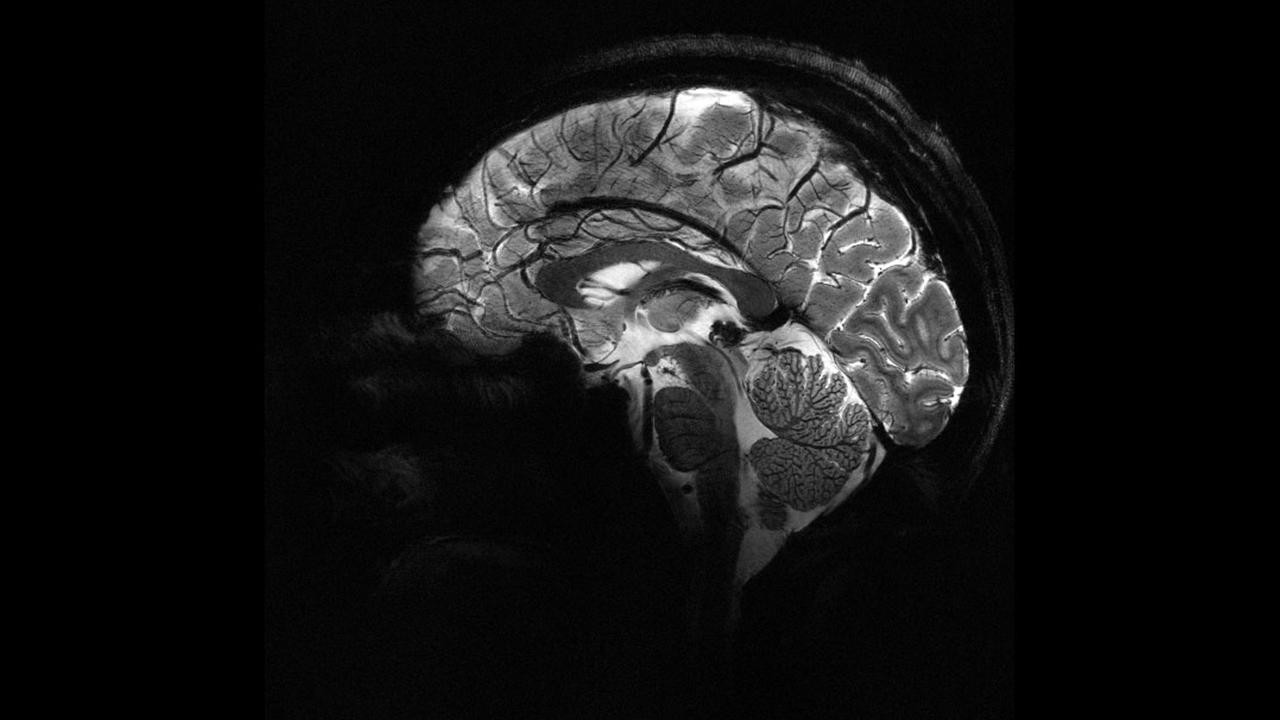

Bilim insanları, uzun yıllardır insan beynini diğer primatlarla karşılaştırarak benzersiz yönlerini anlamaya çalışıyor. Yapılan son araştırma, insan beyninin beklenmedik bir bölgesinin diğer türlerden farklı olduğunu ortaya koydu.

Ancak Oxford Üniversitesi ve Aix-Marseille Üniversitesi'nden bilim insanları, bu kez beynin iç bağlantılarını inceleyerek yeni bir bakış açısı sundu. Araştırmada, insan, şempanze ve makak maymunlarının beyin bağlantı haritaları karşılaştırıldı.

Şempanzeler, bonobolarla birlikte insana en yakın yaşayan akrabalar olarak bilinirken, makak maymunları bilim dünyasında en iyi tanınan primat türleri arasında yer alıyor. Araştırmacılar, manyetik rezonans görüntüleme (MRI) verilerini kullanarak beyindeki "beyaz madde" bağlantılarını analiz etti.

Beyin hücreleri arasındaki iletişimi sağlayan bu bağlantılar, beynin hangi bölgelerinin nasıl çalıştığına dair kritik bilgiler sunuyor.